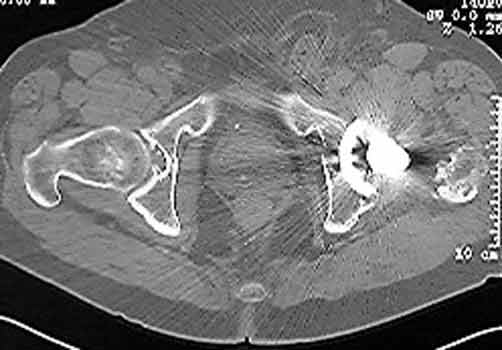

Dislocated femoral component and acetabular cup in grossly loose arthroplasty.  CT guided aspiration to rule out infection.